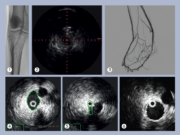

The latest innovation in intravascular ultrasound: Reconnaissance PV .018 OTW digital IVUS catheter

This advertorial is sponsored by Philips.

Intravascular ultrasound (IVUS) is now used in a wide variety of peripheral vascular interventions after having first been utilized...

Use of IVUS reduces patient risk of MALE or death by up to 28%:...

The benefits of utilizing intravascular ultrasound (IVUS) in peripheral vascular interventions has been widely demonstrated in the literature. In...